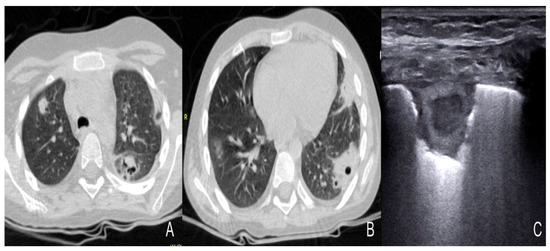

- Grabala, J.; Grabala, M.; Onichimowski, D.; Grabala, P. Possibilities of using ultrasound for diagnosis of invasive pulmonary mucormycosis—A case study. Pol. Ann. Med. 2017, 24, 224–227. [Google Scholar] [CrossRef]

- Panigrahi, M.K.; Manju, R.; Kumar, S.V.; Toi, P.C. Pulmonary mucormycosis presenting as nonresolving pneumonia in a patient with diabetes mellitus. Respir. Care 2014, 59, e201–e205. [Google Scholar] [CrossRef]